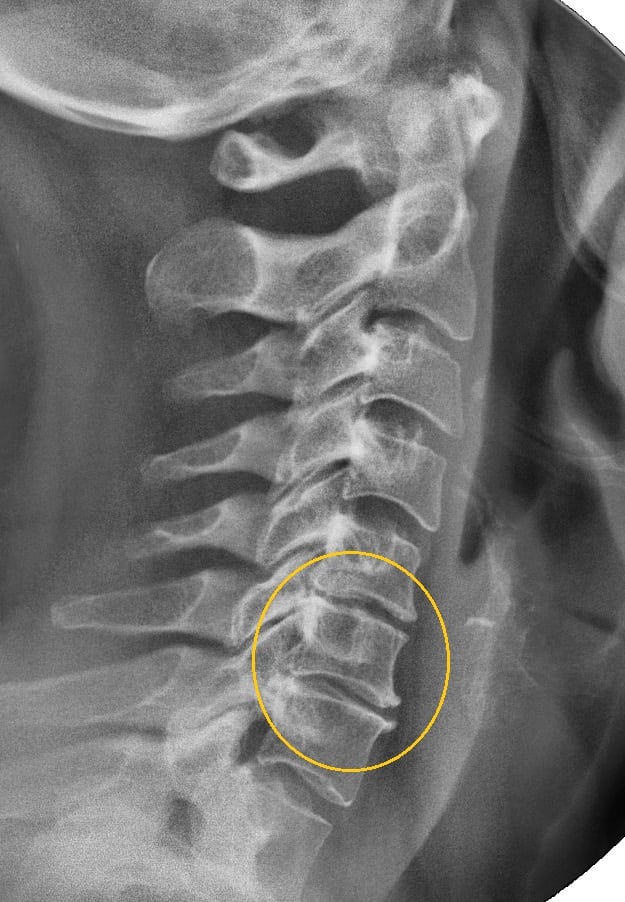

Диагноз выставляется на основании внешнего осмотра пациента, его жалоб, наличия в анамнезе системных заболеваний, предшествующих травм. На шейно-плечевой остеохондроз указывают синюшный оттенок кожи, отечность, изменения контуров пораженных позвонков. Наиболее информативным инструментальным диагностическим методом является рентгенография.

Рентгеновский снимок больного остеохондрозом.

По полученным трехмерным изображениям можно с высокой точностью установить локализацию деструктивно-дегенеративного процесса, стадию его течения, степень повреждения костных, хрящевых тканей, связочно-сухожильного аппарата. Дифференциальная диагностика проводится для исключения артрита, остеомиелита, остеопороза, артроза.